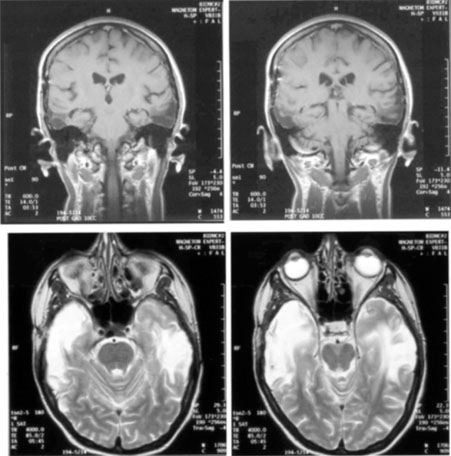

OPTIC TRACTS The optic tract is the continuation of the anterior visual system from the optic chiasm to the LGN. Only the contralateral hemifield is represented. The decussated nasal retinal fibers are not initially well aligned topographically with the other eye's temporal retinal fibers, but retinal correspondence improves towards the termination of the tract at the lateral geniculate nucleus (LGN). The retinotopic map is also tilted in the optic tracts, so that the macula is represented dorsally, inferior retina (superior visual field) laterally, and superior retina (inferior visual field) medially (see Chapter 4, Fig. 9).1 The magnocellular and parvocellular axons also may be segregated, with magnocellular axons more ventral.2 Both of these topographies are mirrored in the LGN. The main vascular supply of the optic tract is the anterior choroidal artery. The functional anatomy of the optic tract is reflected in several important clinical findings. First, partial lesions cause contralateral homonymous defects that can be markedly incongruous (different patterns of visual loss in the two eyes) because of the poor topographic alignment of the two retinal maps (Figs. 1 and 2).3,4 In contrast, lesions of the optic radiations cause only mild incongruity and striate lesions are highly congruous. Complete transection of the optic tract leads to congruous complete hemianopia, although this is less frequent than partial lesions. Reduced acuity with an optic tract lesion indicates bilateral tract damage or extension of the lesion to the optic chiasm or optic nerves.4,5 Second, because the axons in the optic tract originate from retinal ganglion cells, damage to the tract causes optic atrophy over time. This is present in both eyes, but because only half or less of the axons of each eye are affected, the atrophy is less severe than with most optic neuropathies. Also, the pattern of optic atrophy differs between the eyes. In the eye with temporal field loss, the axons from the nasal retina are affected. The fibers from the nasal periphery enter the nasal side of the disc, whereas those from the nasal macula enter the temporal disc in the papillomacular bundle. Atrophy is seen in these nasal and temporal wedges of the disc but the superior and inferior sectors are spared, because these contain fibers from the temporal retina. The result is “bow-tie” optic atrophy (see Fig. 1). In contrast, atrophy in the eye with nasal field loss affects the superior and inferior wedges and papillomacular bundle, but not the nasal wedge. This appears as diffuse or temporal disc pallor. Another distinctive optic disc picture occurs in the eye with temporal field loss when a mass lesion causes papilledema and compresses the optic tract. Disc swelling occurs in the superior and temporal disc but not in the atrophic bow-tie regions, creating “twin-peaks” papilledema (see Fig. 2).6,7 Third, because fibers for the pupillary reflex also travel in the optic tract, often there is a relative afferent pupillary defect (RAPD). With a significantly incongruous hemianopia, the RAPD may be in the eye with greater visual loss. With a complete tract lesion the RAPD is in the eye with temporal field loss,4,8 because the temporal hemifield is larger and there are slightly more axons from the nasal than temporal retina (ratio 53:47). The RAPD is a useful sign in optic tract hemianopia because it may be present at a time when optic atrophy has not yet developed (see Chapter 15).9 Other reported pupillary abnormalities include Wernicke's hemianopic pupil, which is an intraocular afferent pupil defect, with less pupillary constriction from light on the hemianopic hemiretina compared to light on the intact hemiretina. Wernicke's hemianopic pupil is difficult to elicit at the bedside because of intraocular light scatter,3 although it may be seen with computerized pupillometry (Fig. 3). The combination of optic atrophy, RAPD and field incongruity is important to recognize with homonymous hemifield defects, because it changes the differential diagnosis of hemianopia (Fig. 14). Most hemifield defects from lesions of striate cortex or the optic radiations result from vascular disease or other intracerebral pathology. Most optic tract lesions are compressive extrinsic masses, with a differential diagnosis similar to that for optic chiasmal lesions (see Chapter 6). In fact, patients with combined damage to the optic tracts, chiasm, and nerve are not rare.4,10–13 Pituitary adenomas, giant aneurysms of the internal carotid artery, meningiomas, and craniopharyngiomas are the chief causes of optic tract dysfunction. The investigation of choice is imaging of the parasellar region, with coronal and axial sections and contrast administration. Less common lesions include inflammatory conditions such as multiple sclerosis3,11,14,15 and sarcoidosis (see Fig. 1).16 Intrinsic optic pathway gliomas may occur in the optic tracts. Vascular lesions are rare, but there are reports of cavernous angiomata10,17 or arteriovenous malformations.18 Optic tract infarction can complicate anterior temporal lobectomy, possibly from vasospasm of the anterior choroidal artery.19 Trauma can affect the optic tract.3 Radiotherapy of pituitary tumors may be followed years later by optic tract necrosis.13 Optic tract dysfunction is a side effect of alpha-interferon.20 On occasion there is congenital absence of the optic tract 21; such patients are often unaware of their hemianopia. Associated abnormalities are unusual.3 These include endocrine disturbances from hypothalamic dysfunction and memory impairment from temporal lobe involvement,22 reflecting the proximity of the optic tracts to these structures (see Chapter 4). LATERAL GENICULATE NUCLEUS The LGN is a subnucleus in the ventro-postero-lateral corner of the thalamus. Neighboring thalamic subnuclei include the medial geniculate nucleus ventromedially, ventral posterior nucleus dorsomedially, and pulvinar superiorly and dorsally. The medial geniculate nucleus gives rise to the acoustic radiations, which pass by the dorsomedial aspect of the LGN on their way to the auditory cortex in the temporal lobe. The optic radiations arise from the dorsolateral surface of the LGN. Ventrally, the hippocampus and parahippocampal gyrus face the LGN across the ambient cistern and the inferior horn of the lateral ventricle. The LGN has a dual blood supply: the anterior choroidal artery, a branch of the internal carotid artery, and the lateral choroidal artery, a branch of the posterior cerebral artery. The anatomy of the vascular territories within the LGN has been debated. Initial studies suggested that the anterior choroidal artery supplied the medial LGN as well as the optic tract and the lateral choroidal artery the lateral LGN. However, experience with surgical arterial lesions concluded that the anterior choroidal artery supplied both the lateral and medial aspects and the lateral choroidal artery supplied the hilus and midzone of the LGN. In addition to its function as a relay in the visual pathway, the LGN is also a site of modulation, by back-projections from visual cortex23,24 and afferent projections from the brainstem reticular formation and superior colliculus.25 Some of the corticofugal input influences the stimulus selectivity of LGN neurons.24 Others postulate that these nonretinal inputs play a role in gating visual transmission through the LGN, and thus participate in selective attention.23 The LGN is a triangular shaped structure with six roughly horizontal layers containing segregated inputs from the two eyes (see Chapter 4, Fig. 8). The ventral two layers are the magnocellular layers, whereas the other four layers are the parvocellular component; these differ in many structural and functional aspects (see Chapter 4). The LGN has a retinotopic pattern that is a continuation of that found in the optic tract. The macula is represented in a dorsal wedge, including the hilum and projecting posteriorly, whereas the most peripheral fibers are located ventrally. Superior retinal fibers (contralateral inferior visual quadrant) are in the medial horn and inferior retinal fibers (contralateral superior visual quadrant) are in the lateral horn. Because the LGN is small and relatively secluded, lesions here are rare. Its intimate relation to the optic tract and optic radiation make it difficult to be certain that a visual defect results from LGN damage rather than damage to these structures. Indeed, visual field defects from purported LGN lesions resemble visual field defects from optic tract or optic radiation lesions. Three main types of hemianopic defects have been described. The first is an incongruous hemianopia, much like that seen with optic tract lesions, reflecting the continued segregation of ocular inputs in the LGN. The other two patterns are sectorial hemianopias reflecting the unusual territorial division between the anterior and lateral choroidal arterial supplies. With lateral choroidal ischemia, the hilum and middle zone of the LGN are affected, causing a wedge-shaped visual defect straddling the horizontal meridian (Fig. 4).26 With anterior choroidal ischemia, the lateral and medial tips of the LGN are infarcted, resulting in the reverse defect, loss of the superior and inferior aspects of the contralateral hemifield with sparing around the horizontal meridian.27,28 Unusual cases of presumed bilateral LGN damage have presented with an “hourglass” shape to either the visual field defect29,30 or the region of spared vision.31 Optic atrophy often accompanies LGN lesions. If there is damage to almost all of the LGN, the optic atrophy has a similar appearance to that seen with optic tract lesions. If there is partial damage causing sectorial hemianopias, then the optic atrophy may be more subtle and restricted to the relevant sectors of the disc.26,27 However, because the afferent fibers subserving the pupillary light reflex already have departed for the pretectum, there is no RAPD with lesions of the LGN. With incongruous hemianopia and optic atrophy, this is the only feature that permits distinction between optic tract and LGN lesions. A variety of pathologies have been reported with LGN lesions. Infarction is the most likely cause of sectoranopia, given the dependence of such defects on the vascular anatomy,26,27 but astrocytomas and arteriovenous malformations are also reported. Furthermore, the LGN appears to be a target of central pontine myelinolysis, a syndrome associated with excessively rapid correction of hyponatremia.29,30,32 LGN damage rarely is a parainfectious complication of traveler's diarrhea.31 OPTIC RADIATIONS The optic radiation may be affected anywhere in its course (see Chapter 4); the type of visual field defect reflects the site of damage. Ischemic or hemorrhagic lesions of the internal capsule affect the optic radiation while it is still a relatively compact bundle, usually causing a complete homonymous hemianopia. A similar defect can arise from damage close to the termination in striate cortex (Fig. 5). Lesions of the ventral fibers in the anterior temporal lobe cause a contralateral superior visual quadrant defect (Fig. 6). Most often this defect aligns on the vertical meridian, with variable extension toward the horizontal meridian and central vision.33 Lesions of the dorsal fibers in the parietal lobe cause an inferior visual quadrant defect (Fig. 7). Because there is no sharp demarcation of the dorsal fibers from the ventral fibers in this portion of the posterior pathway, the defect seldom aligns along the horizontal meridian.33 Overall, quadrantanopia is more frequent with lesions of striate cortex.33 Lesions of the temporal lobe more than 8 cm posterior to its anterior tip can affect both upper and lower radiations. Small lesions also may affect certain portions of the radiations and spare others; for example, damage to the midportion of the optic radiation can mimic the sectoranopias of LGN lesions (Fig. 8).34 Although there can be some incongruity to the visual field defects of optic radiation lesions, this is less marked than the incongruity with optic tract lesions. Unlike lesions of the retino-geniculate pathway or LGN, lesions of the geniculostriate axons do not lead to optic atrophy (with the exception of some congenital lesions, through trans-synaptic degeneration) or pupillary defects. However, frequently there are other signs of cerebral damage,33 especially if the lesion is large. Thus, temporal lobe lesions cause superior quadrantic defects and sometimes also complex partial seizures, auditory or complex visual hallucinations (some of which may be seizures), memory problems, or a Wernicke's aphasia if the dominant hemisphere is involved. Parietal lesions with mainly inferior quadrantic defects may cause cortical sensory disturbances, such as impaired two-point discrimination and graphesthesia, and impaired smooth pursuit toward the side of the lesion. With dominant hemisphere lesions, Gerstmann's syndrome (acalculia, finger anomia, right-left disorientation, and agraphia) may occur, as may a variety of aphasic syndromes, including alexia with or without agraphia, Wernicke's aphasia, or global aphasia. The differential diagnosis of optic radiation lesions reflects the variety of cerebral hemispheric pathologies. Unlike lesions of the optic tract, most are infarcts in the posterior cerebral or middle cerebral artery territories. Tumors, vascular malformations, infections, and leukodystrophies are also possibilities. The temporal profile of the illness often is the major clue to the etiology. STRIATE CORTEX The primary visual area in the medial occipital lobe goes by several names: Brodmann's area 17, “visual area 1” or V1, “calcarine cortex,” and “striate cortex” (see Chapter 4). The exact position of striate cortex varies among individuals. Although the parieto-occipital fissure forms a reasonably reliable anterior dorsal boundary, the posterior limit containing the macular representation is more variable, extending from the medial occipital surface over the first one or two centimeters of the posterior surface of the occipital lobe (see Chapter 4, Fig. 10). The main vascular supply of striate cortex derives from the posterior cerebral artery (see Chapter 4, Fig. 15). A parieto-occipital branch supplies the superior calcarine bank, a posterior temporal branch supplies its inferior bank, and a calcarine branch supplies the central region posteriorly; however, individual variation exists.35 Perhaps most importantly, the occipital pole is at the junction (watershed zone) of the vascular territories of the posterior and middle cerebral arteries, and again there is marked variation as to which artery supplies the foveal representation in striate cortex.35 The retinotopic arrangement in striate cortex is well known (see Chapter 4), and confirmed with recent imaging studies of lesions.36 The foveal representation is posterior, at the occipital pole, and the far peripheral field is anterior, on the medial occipital surface.37,38 The superior bank of the calcarine fissure receives input from the inferior visual field, whereas the inferior bank contains the representation of the superior visual field. The most anterior part of striate cortex represents the monocular temporal crescent, the region of temporal field in the contralateral eye that lies beyond the limits of the nasal field (60°) of the ipsilateral eye. As in most of the visual system, there are fewer neurons devoted to peripheral vision than to central vision: Over half of striate cortex is devoted to the central 10° (cortical magnification).36,39 Occipital cortex contains a mixture of monocular and binocular cells arranged in ocular dominance columns, but large separations between the inputs of the two eyes are not present. Visual Field Defects from Striate Lesions Focal destruction of striate cortex produces a homonymous contralateral visual hemifield defect. Unlike the scotomata from lesions of the optic radiations and especially the optic tracts, the hemianopic defects from striate lesions are highly congruent, with virtually identical defects in the two eyes. Complete destruction of striate cortex causes complete visual loss in the contralateral visual hemifield. Because this involves not only peripheral vision but also the contralateral half of the foveal region it is called a macula-splitting homonymous hemianopia. This may occur with posterior cerebral artery ischemia in a patient whose entire striate cortex is supplied by that artery. Macula-splitting hemianopias can occur with complete lesions anywhere along the retrochiasmal visual pathways, and thus lack localizing value (see Fig. 5). Other signs may help in localization. Reading is particularly impaired by involvement of the central 5°.40 Partial lesions of the striate cortex are frequent. With posterior cerebral infarcts, a macula-sparing hemianopia occurs in patients with adequate collateral circulation of the macula region (occipital pole) from the middle cerebral artery (Fig. 9).35 Previously, macula-sparing was thought to result from bilateral representation of a small stripe flanking the vertical meridian, which expanded to as much as 3° at the fovea.41 However, studies of monkey V1 do not find bilateral representation of the hemimaculae,42 and computed tomography (CT) and magnetic resonance imaging (MRI) studies in humans with hemianopia document the correlation of macular sparing with sparing of the occipital pole.43,44 Also, careful perimetry of hemianopes with the scanning laser ophthalmoscope shows that, although there is a slight overlap from the seeing field into the blind field along the meridian, macular sparing of 2° to 5° is only present in some patients.45,46 Therefore sparing more likely reflects the extent of occipital pathology than retinal anatomy. Macula-sparing has some localizing value, because it is seen mainly with lesions of striate cortex. The upper and lower banks can also be involved separately. Ischemia can do this because the banks have separate blood supplies. Upper bank infarcts cause homonymous contralateral inferior quadrantanopia (Fig. 10) and lower bank infarcts cause superior quadrantanopia. Although altitudinal defects have been reported occasionally,47,48 most quadrantic defects do not align at the horizontal meridian, because the upper field merges without interruption into the lower field in the depths of the calcarine fissure. Thus it has been argued that quadrantic defects that respect the horizontal meridian are caused by involvement of area V2, surrounding striate cortex,49 which remains controversial. Quadrantanopias are three times more common with striate lesions than with optic radiation lesions.33 Striate quadrantanopias are more frequently isolated signs but can be associated with other signs of higher cortical visual dysfunction, such as pure alexia or hemiachromatopsia, whereas optic radiation quadrantanopias usually are accompanied by hemiparesis, dysphasia, or amnestic problems.33 Selective lesions can also occur along the anterior-posterior extent of striate cortex. A lesion of the occipital pole alone causes homonymous central hemiscotomata (Fig. 11).44,50 This can occur with watershed infarcts during systemic hypoperfusion. Slightly more anterior lesions in the middle zone of striate cortex cause homonymous peripheral scotomata (Fig. 12). The highly congruent, homonymous nature of these defects and their restriction to one hemifield differentiate these from ocular causes of central or paracentral visual loss. Lesions with such small field defects can be missed on CT.43 MRI with coronal sections through the occipital lobes should be performed, although even this may miss small lesions, particularly at the occipital pole. A near-complete lesion that spares only the most anterior portion of V1 causes a nearly pathognomonic field defect, hemianopia with sparing of the monocular temporal crescent (Fig. 13). The hemianopia involves the whole nasal hemifield of the ipsilateral eye but the temporal hemianopia of the contralateral eye spares a crescent-shaped island of vision in the far periphery.51 This is the monocular temporal crescent, the region of the visual field that is represented in the temporal field of one eye but not the nasal field of the other. The initial sense of incongruity may raise suspicions of an optic tract lesion; however, the absence of optic atrophy and RAPD, the high congruity of the homonymous defect inside 60°, and the location of the crescent outside 60° eccentricity, indicate that the lesion must be in striate cortex. The converse defect, a monocular temporal crescentic scotoma, can occur with a retrosplenial lesion, along the parieto-occipital sulcus.52 Most striate lesions are infarction, mainly from posterior cerebral artery occlusion (Fig. 14), with sudden onset visual loss and sometimes headache.53 In about half, the visual field defect is the only deficit,53 but in others damage to medial occipito-temporal regions causes amnesia, prosopagnosia, and color perception defects. A syndrome of agitated delirium and hemianopia occurs with lesions of the medial occipital lobe, parahippocampus, and hippocampus.54–56 Brainstem signs include impaired level of consciousness, III nerve palsy, dysarthria and hemiplegia.53 Causes of ischemia are most frequently cardiac emboli and vertebrobasilar occlusive disease; migraine is a rare cause of permanent defects.53 Hemorrhage, vascular malformations, primary and secondary malignancies are much less common.33 Bilateral lesions of striate cortex are not rare. Focal midline lesions such as tumors or traumatic injury may affect both striate cortices concurrently, because the right and left striate cortices face each other on the medial occipital surface. The most common cause, however, is posterior circulation ischemia.57 This can affect both striate cortices either simultaneously or sequentially,57 because the right and left posterior cerebral arteries have a common origin from the basilar artery. Twenty-two percent of patients with a unilateral occipital infarction develop bilateral infarction over 3 years.58 Bilateral incomplete hemianopia is distinguished from bilateral optic nerve or ocular disease by the high congruity of the visual fields and step defects along the vertical meridian which indicate the hemifield nature of the visual loss (Fig. 15).57 Such steps are important to seek with a skilled perimetrist, but even so they can be difficult to demonstrate with bilateral hemiscotomata from occipital pole lesions.59 Bilateral quadrantanopias can occur,47,48 often in patients with prosopagnosia and achromatopsia for example, and may mimic the altitudinal defects of optic neuropathy. Cerebral Blindness Cortical blindness is a loosely used term, at times referring to visual loss from occipital lobe damage, even if the loss is incomplete. Hence hemianopia or bilateral quadrantanopia has been called cortical blindness. It is best reserved for bilateral complete or severe hemianopia, with acuity at light perception only or worse, and no detectable peripheral vision. Because lesions may involve both gray and white matter, cerebral blindness is a better term. Cerebral blindness can be persistent or transient. The most frequent cause of persistent cerebral blindness is cerebrovascular infarction.60 In addition to the common causes of emboli or atherosclerosis, it has been reported with vertebrobasilar arteritis,61 subclavian steal,62,63 and hypotension from antihypertensive medication.64,65 Cerebral blindness can complicate cardiac surgery, through hypotension or emboli.60 A rare vascular cause is rupture of occipital mycotic aneurysms with endocarditis.66 Cerebral blindness is distinguished from ocular disease by both normal pupillary light responses and normal fundoscopic examination. These may lead to an erroneous diagnosis of factitious visual loss. Associated signs of damage to parietal or temporal structures help to confirm cerebral blindness but may not always be present. Visual evoked potentials are of limited diagnostic value. They can be altered voluntarily by subjects without visual loss67 and can be normal in patients with striate lesions.68,69 They cannot differentiate between blind and seeing children with neurologic disease,70 and normal or abnormal results do not predict visual outcome.60,71 Absent evoked responses are rare and may only occur early in the course.70 Absent alpha rhythm on electroencephalography72,73 is reportedly a more sensitive diagnostic sign than abnormal visual evoked potentials.60 CT scans can be normal, but modern MR imaging with coronal images through the occipital lobe should reveal most striate or optic radiation lesions with complete and persistent visual loss (Fig. 16). Single photon emission computed tomography (SPECT) scans may reveal bilateral functional defects in cases with unilateral MRI lesions.74